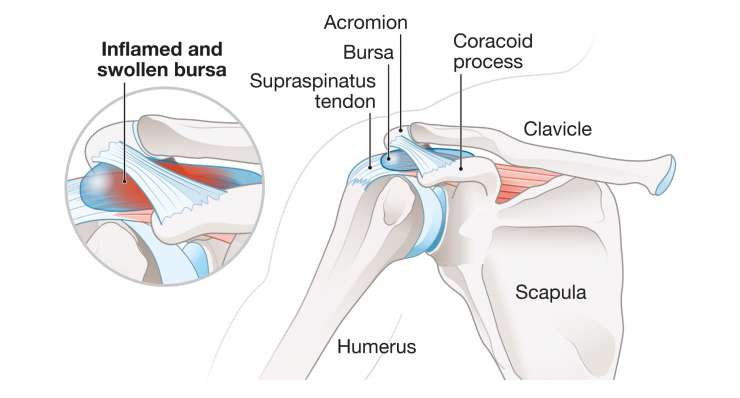

бурсит

Проф. д-р мед. Фрэнк Мартечшлегер обычно лечит бурсит плеча консервативными методами с помощью противовоспалительных средств, а при хроническом течении заболевания также с помощью артроскопии, чтобы навсегда избавиться от боли.